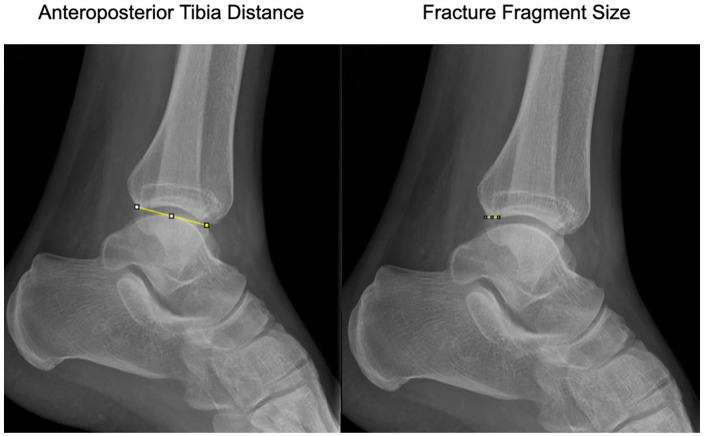

Methods: Morphology of the PMF was categorized initially by the CT scan as classified by Mason and Molloy on 180 trimalleolar ankle fractures. PM fracture fragment size on the lateral radiograph were compared to their respective 3D surface rendering CT reconstructions, by two independent observers. Morphology of the PMF was assessed using all preoperative radiographs as compared to 3D SR CT.

Results: On comparison of fracture fragment morphology, all fractures had poor categorization by plain radiographs although rotational pilon fractures (type 2A and 2B fractures) had the worse sensitivity and specificity (below 33% and below 50%, respectively). Radiographs underestimated joint involvement in type 2B fracture patterns because of the underappreciation of the posteromedial fragment.

Conclusion: This study shows that the use of plain radiographs to categorize morphology of PMFs is poor. The study adds to the ever-growing body of evidence on the inaccuracy of using plain radiographs in PMFs to plan treatment. Additional CT imaging is imperative to allow for appropriate treatment planning in the management of PMF. Smaller fracture fragments are more susceptible to inaccuracies, especially the rotational pilon subtypes (2A and 2B) because of the obliquity of the posteromedial fragment to the plane of the X-ray source.